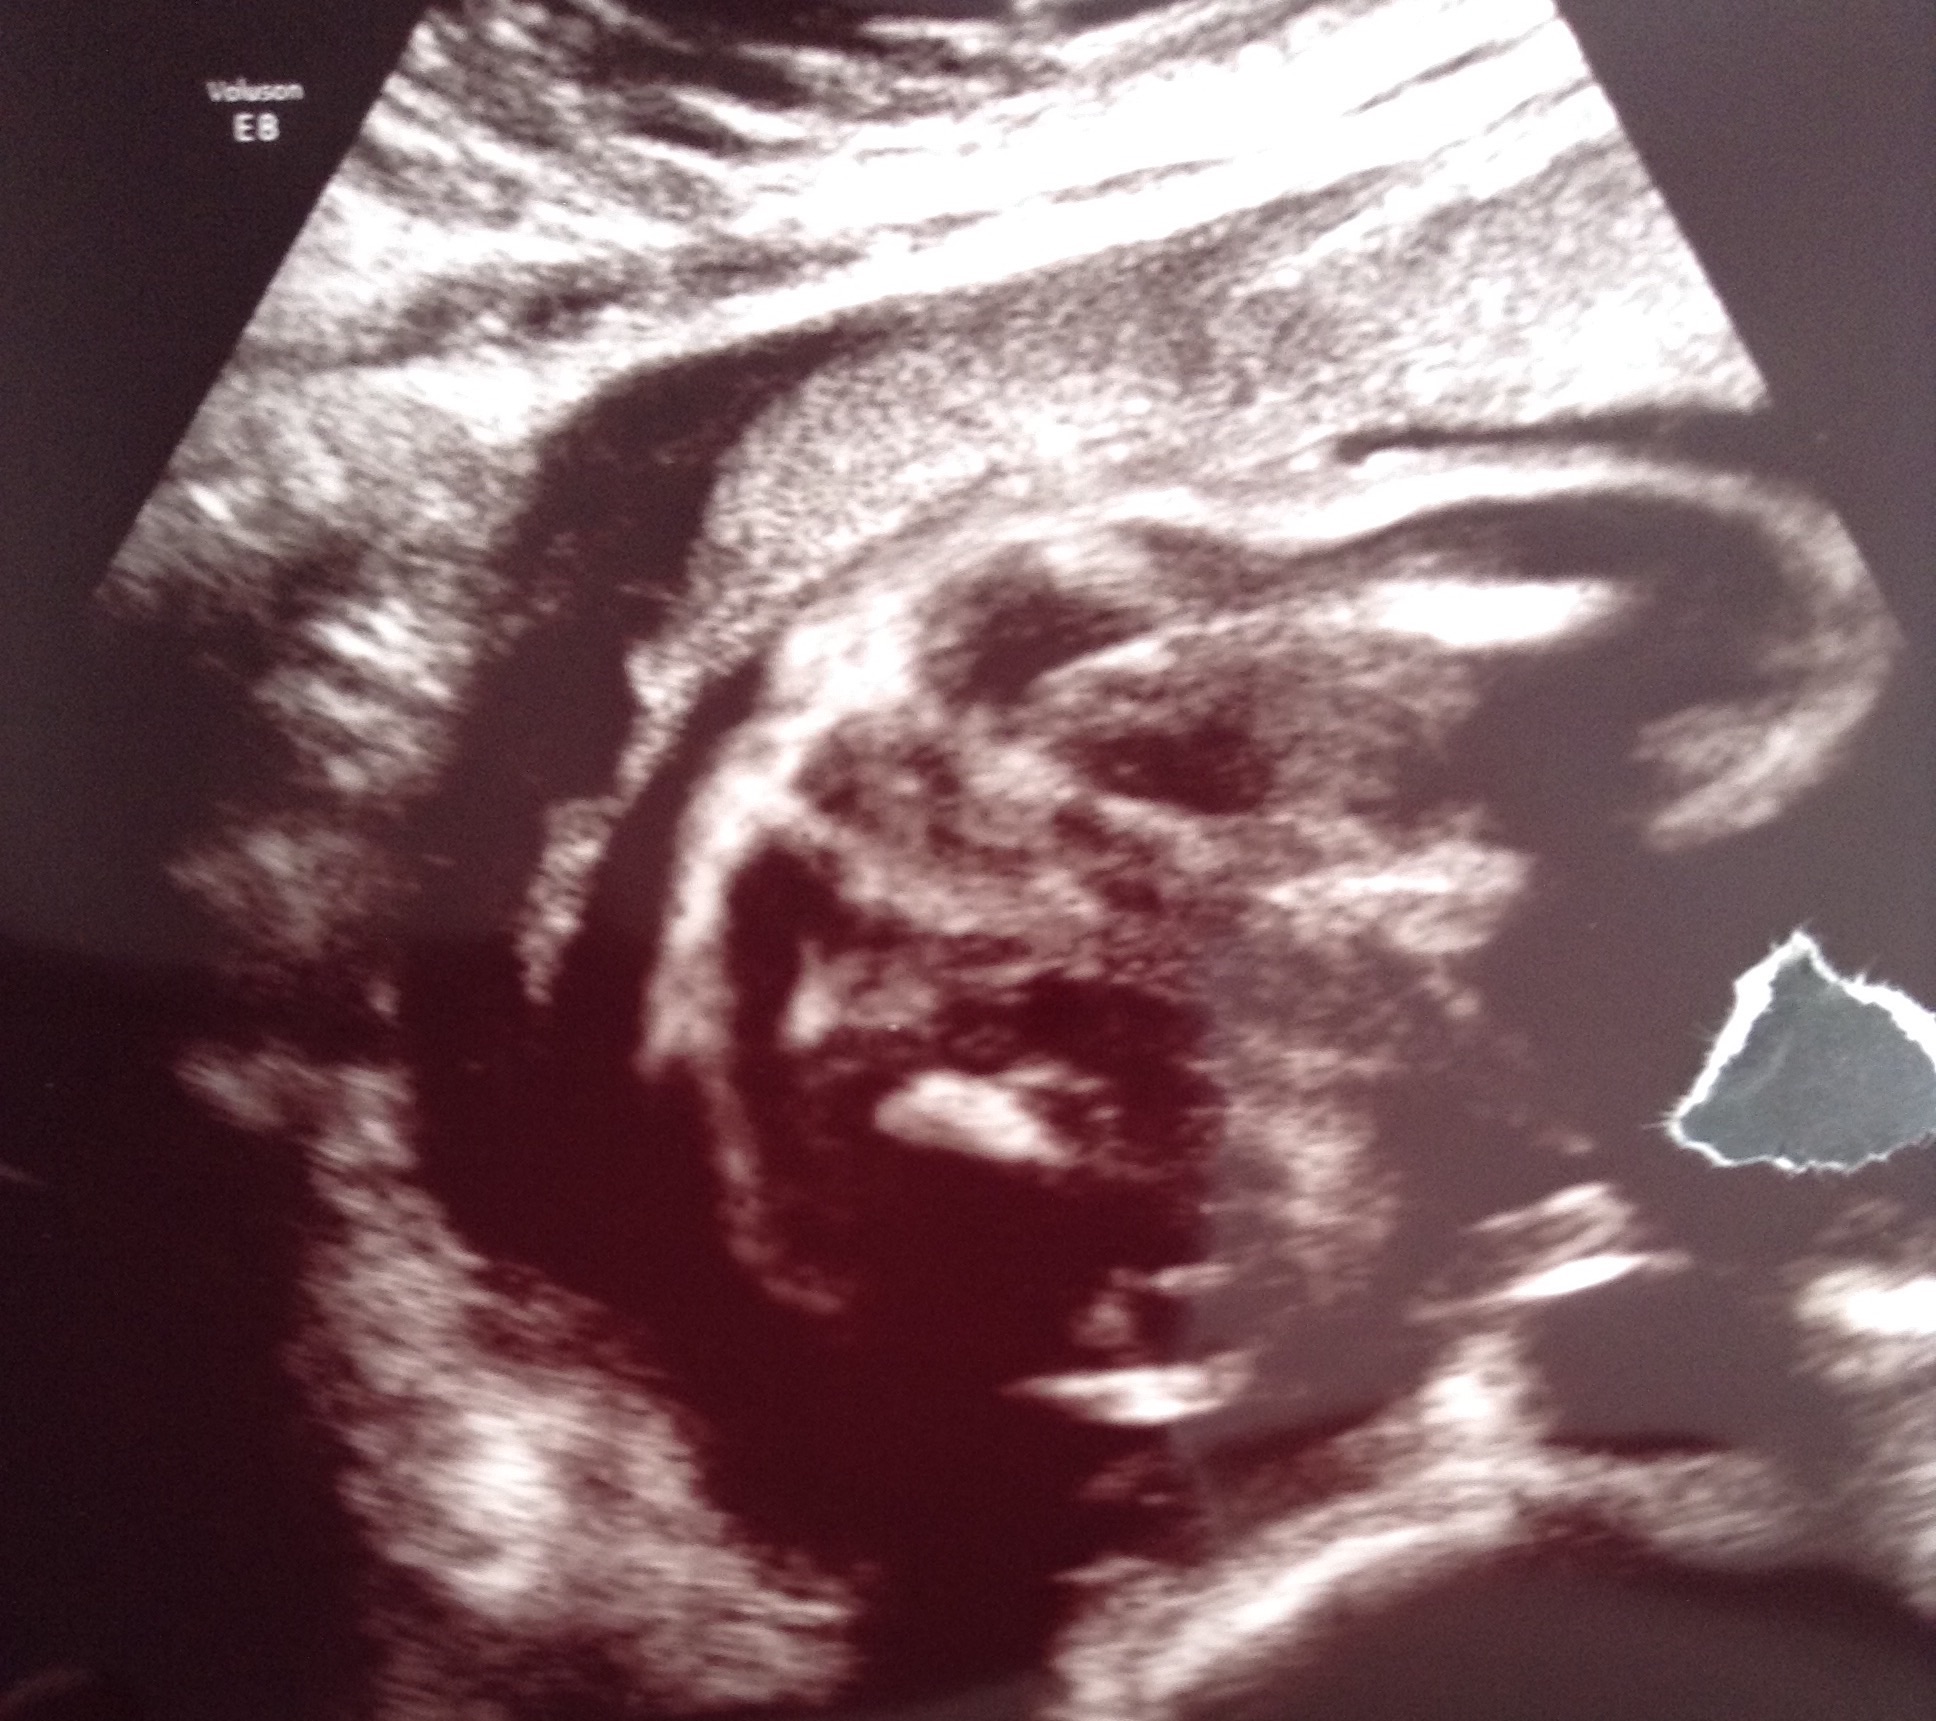

potty shot 26 weeks help!

Any ideas? I don't think I see anything clear ..